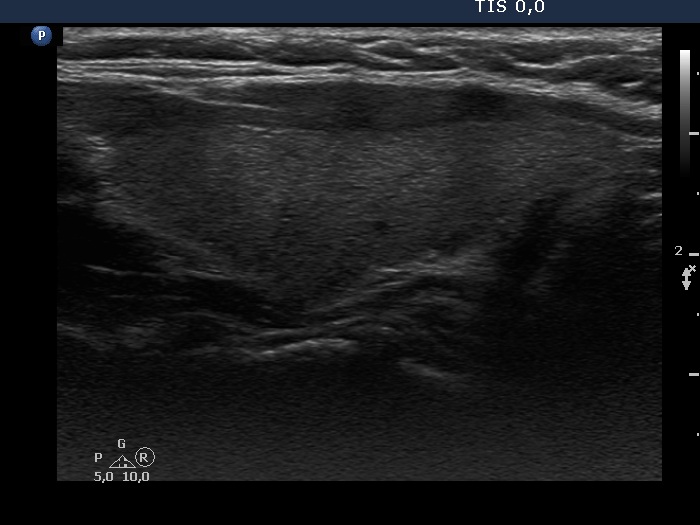

Consecutive patients with the final diagnosis of Hashimoto's thyroiditis - case 36 (574) (ultrasonographic picture 5)

Left lobe, longitudinal view.